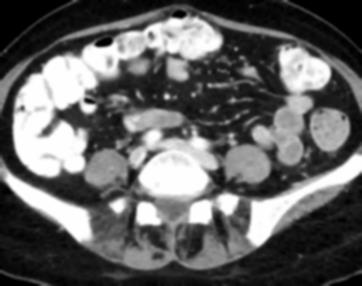

Due to the constraints of the imaging device and high cost in operation time, computer tomography (CT) scans are usually acquired with low intra-slice resolution. Improving the intra-slice resolution is beneficial to the disease diagnosis for both human experts and computer-aided systems. To this end, this paper builds a novel medical slice synthesis to increase the between-slice resolution. Considering that the ground-truth intermediate medical slices are always absent in clinical practice, we introduce the incremental cross-view mutual distillation strategy to accomplish this task in the self-supervised learning manner. Specifically, we model this problem from three different views: slice-wise interpolation from axial view and pixel-wise interpolation from coronal and sagittal views. Under this circumstance, the models learned from different views can distill valuable knowledge to guide the learning processes of each other. We can repeat this process to make the models synthesize intermediate slice data with increasing inter-slice resolution. To demonstrate the effectiveness of the proposed approach, we conduct comprehensive experiments on a large-scale CT dataset. Quantitative and qualitative comparison results show that our method outperforms state-of-the-art algorithms by clear margins.